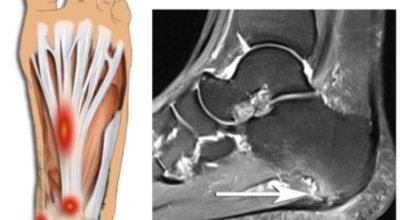

족저 근막이란 발가락 시작지점부터 발뒤꿈치뼈까지 발바닥 전체를 감싸고 있는 두꺼운 막을 말해요. 족저 근막은 발바닥 아치를 지속시켜 발바닥이 지면을 내딛음으로써 나타나는 충격을 흡수하는 중요한 역할을 수행하고 있어요. 이 족저 근막에 일차적으로 서서히 조직 손상이 일어나고 계속적인 활동으로 인해 염증이 커지면서 발 뒤꿈치 부근 통증을 유발하게 되는데 염증은 무리하고 반복적인 동작, 과도한 사용으로 마찰에 의해 발생해요.

주요 증상은 통증으로 발뒤꿈치 안쪽이 아주 아프며, 맨발로 바닥을 걸을 때 걸음을 내딛을 때마다 통증이 있어요. 가장 심한 통증은 아침에 일어나 첫 걸음을 뗄 때인데, 밤에 족저근막이 수축하다가 발에 체중이 가해지면서 갑자기 늘어나는 현상입니다.

비수술적 치료 방법에으로 보조기, 체외충격파, 스트레칭, 스테로이드 주사요법, 비스테로이드성 소염진통제 등이 여러 방법들이 있어요. 족저근막염 발생초기에는 스트레칭을하여 족저근막 또는 아킬레스건을 효과적으로 증가시키는 것만으로 추가적인 피해를 방지할 수 있죠. 그리고 보조기를 착용해서 뒤꿈치에 가해지는 충격을 완화 시킬 수 있어요. 발에 부종이 생긴 경우 진통주사를 이용해서 치료할 수 있어요. 수술적 치료로 들어가기 전 체외충격파를 이용해서 증상완화의 효과를 볼 수 있다고 해요.